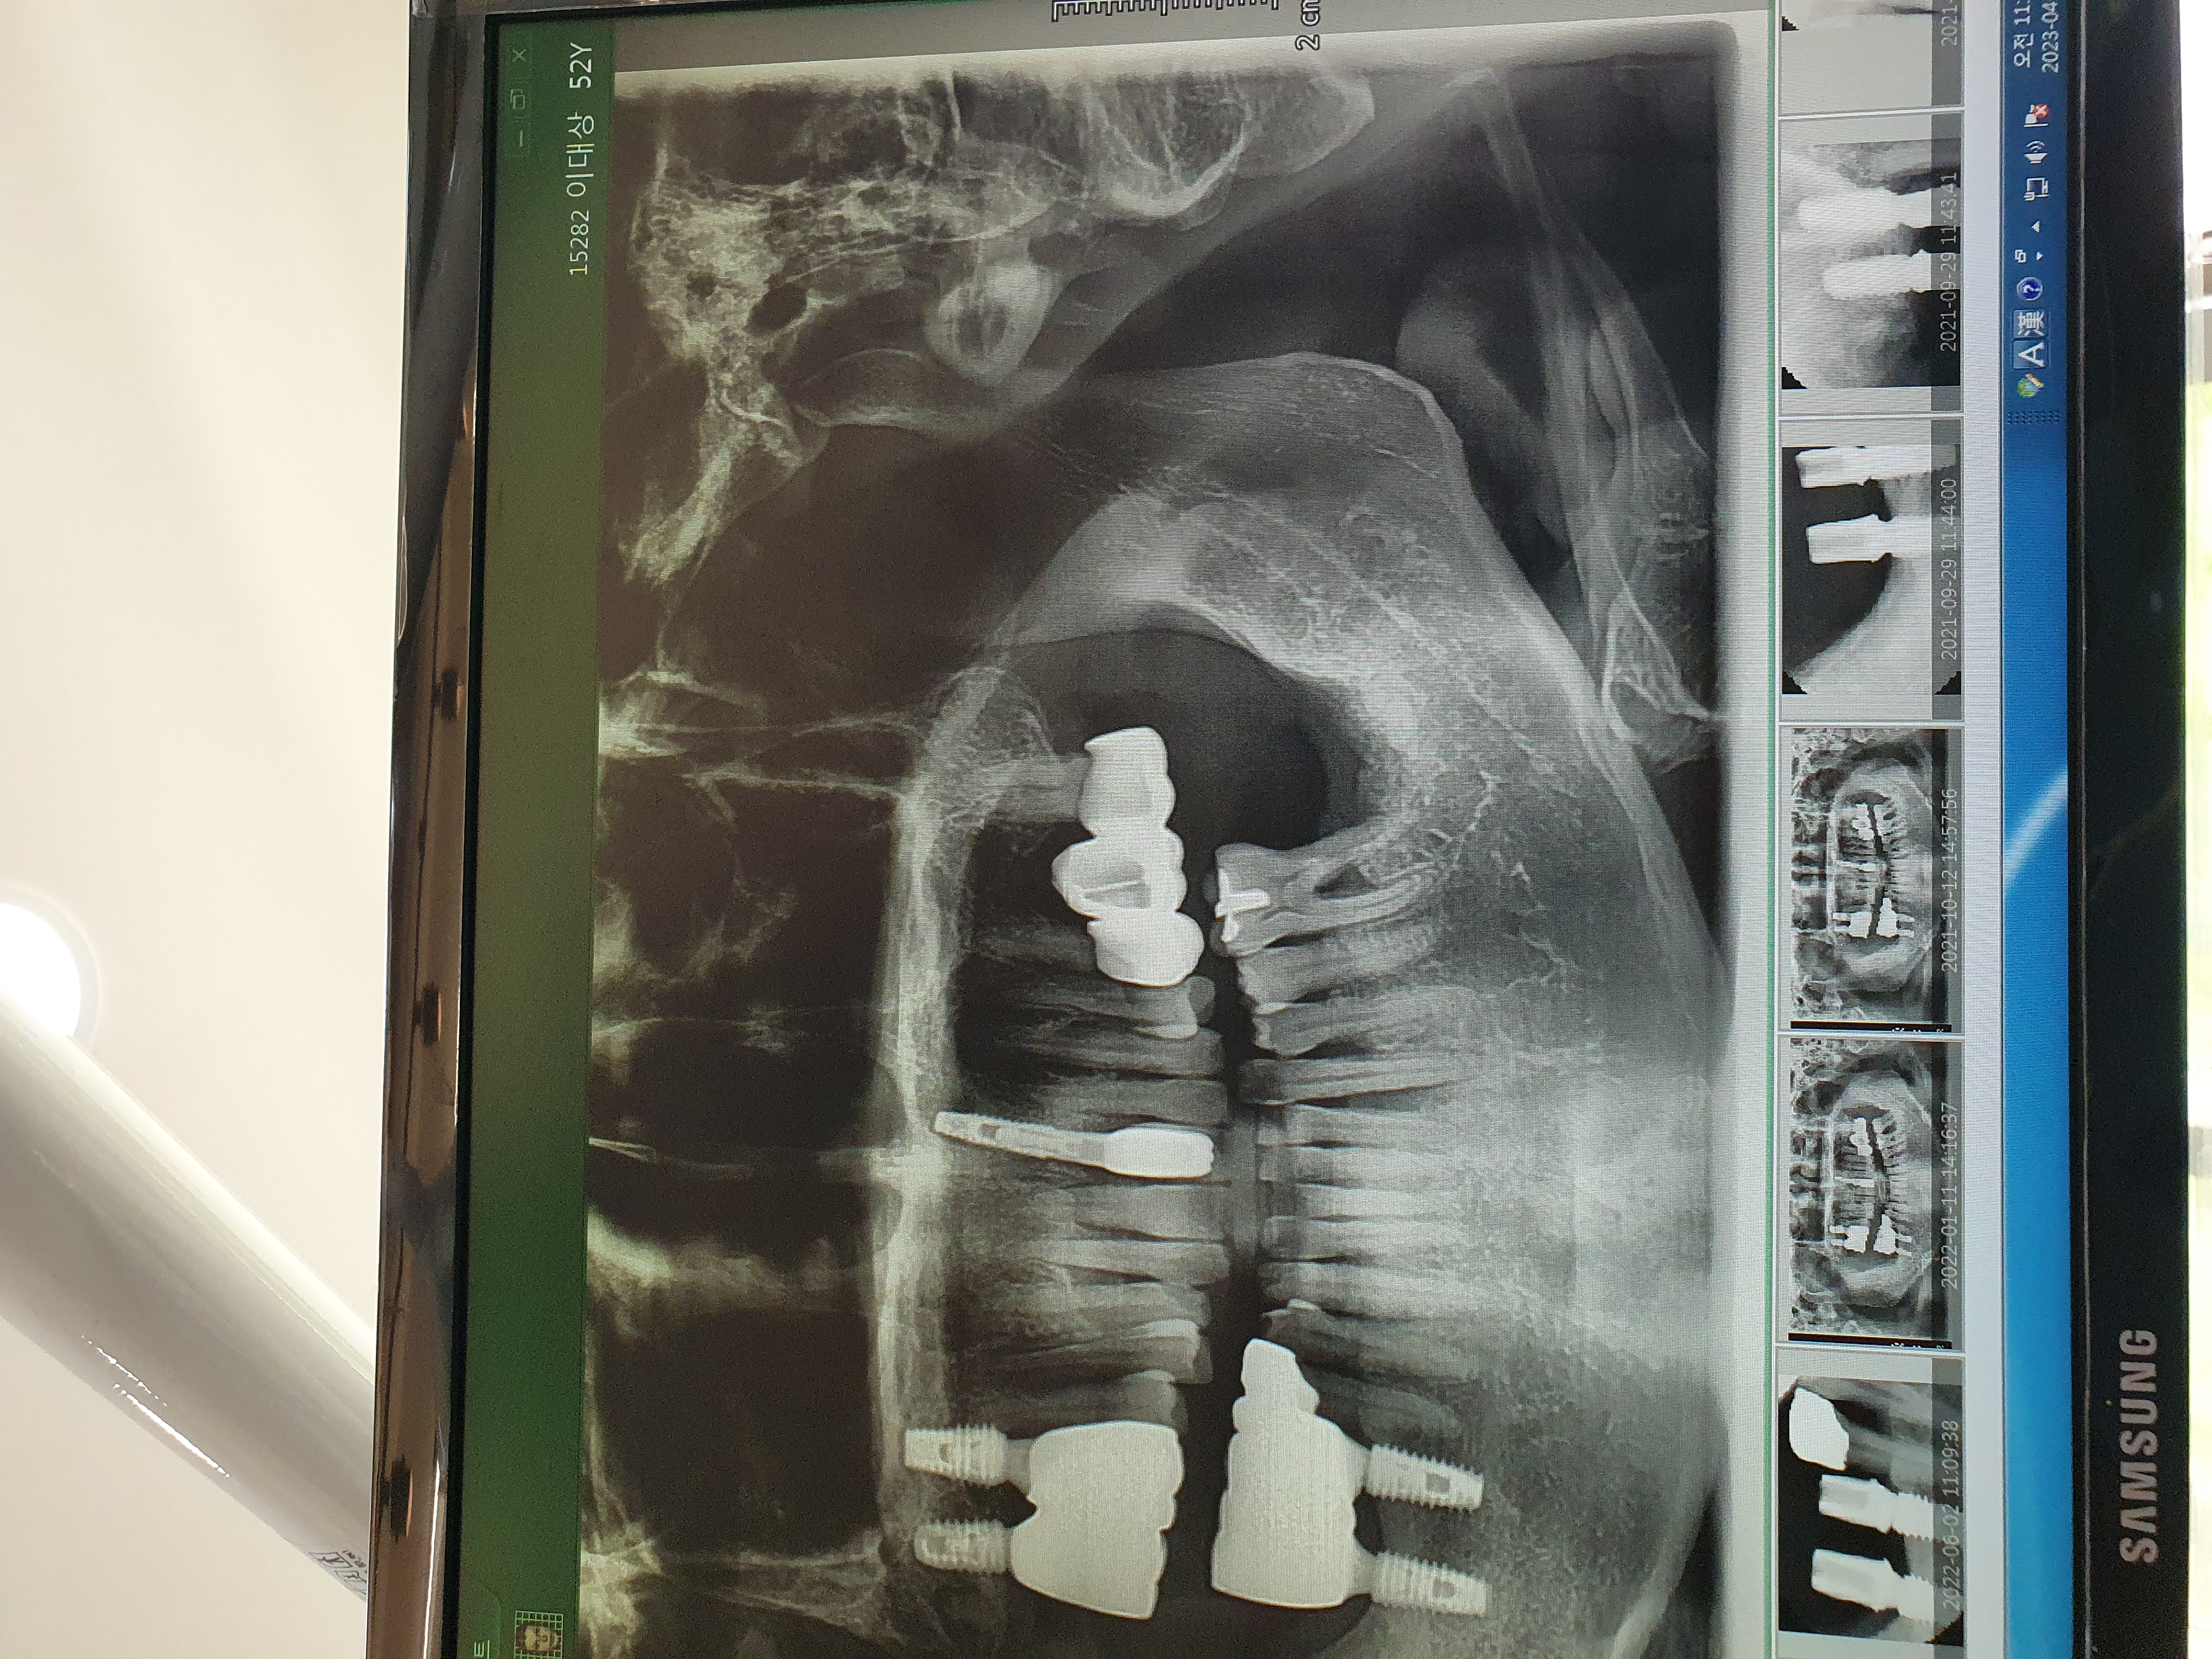

전

후

친절한 설명과 상담후 당일 임플란트 시술 진행 했습니다. 저렴하고 힙리적인 가격 만족 합니다